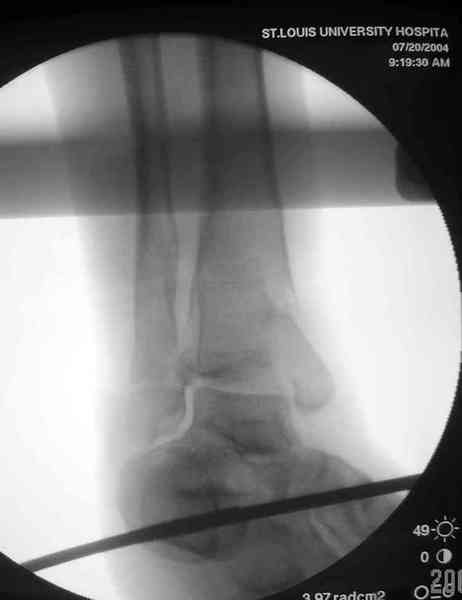

Аутокость является самым надежным материалом, но при желании можно применить синтетический заполнитель Osteoset Pallets - структуральный материал, по аннотации материал через определенное время интегрируется в кость.

Здесь выставлена пара случаев перелома пилона, оба

случая леченные этапным наружным фиксатором.

Второй случай фиксирован аппаратом Илизарова.